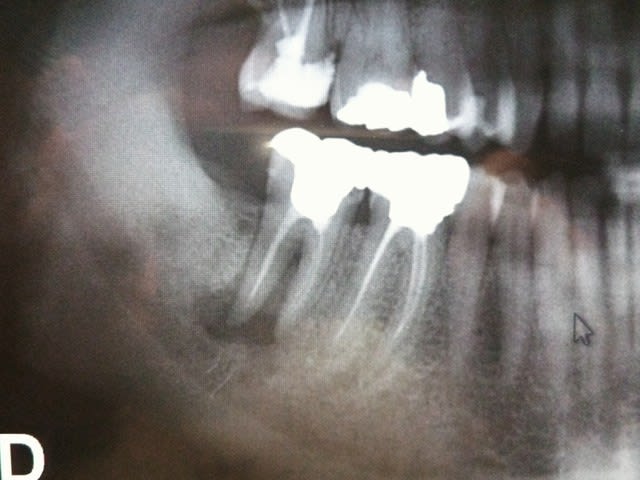

Voilà la radio panoramique d'une patiente, âgée d'un trentaine d'année que j'ai reçu la semaine dernière en consultation.

La 47 présente une image radioclaire à l'apex et la patiente se plaint de douleur à la pression sur cette dent qui ne présente pas de mobilité.

En fait, vu la taille de la lésion (qui en plus est très proche du nerf alvéolaire inférieur), la longueur des racines et la pathologie de la patiente je pense que le RTE ne va pas donner grand chose et sera très compliqué. En plus cette dent est couronnée. Désolée pour la nullité du cas ou du dentiste mais je débute dans le métier donc, au lieu de faire des conneries, je préfère demander l'avis à des personnes plus expérimentées.